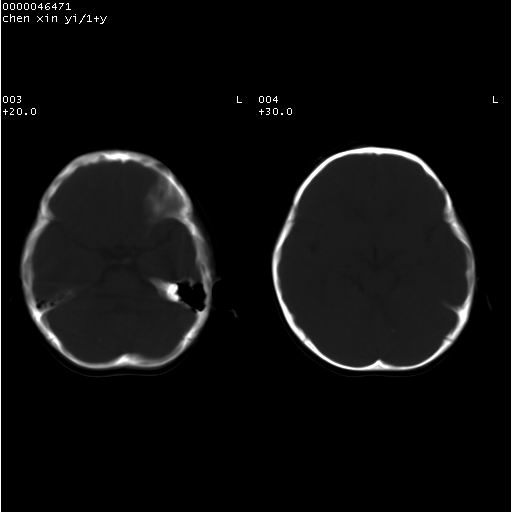

以下是引用zhangzhongshou在2008-4-9 12:54:00的发言:[br]请结合病史,有以下可能1、炎性肉芽肿钙化(含结核)2、寄生虫钙化(含脑囊虫)3、其他良性钙化性病变